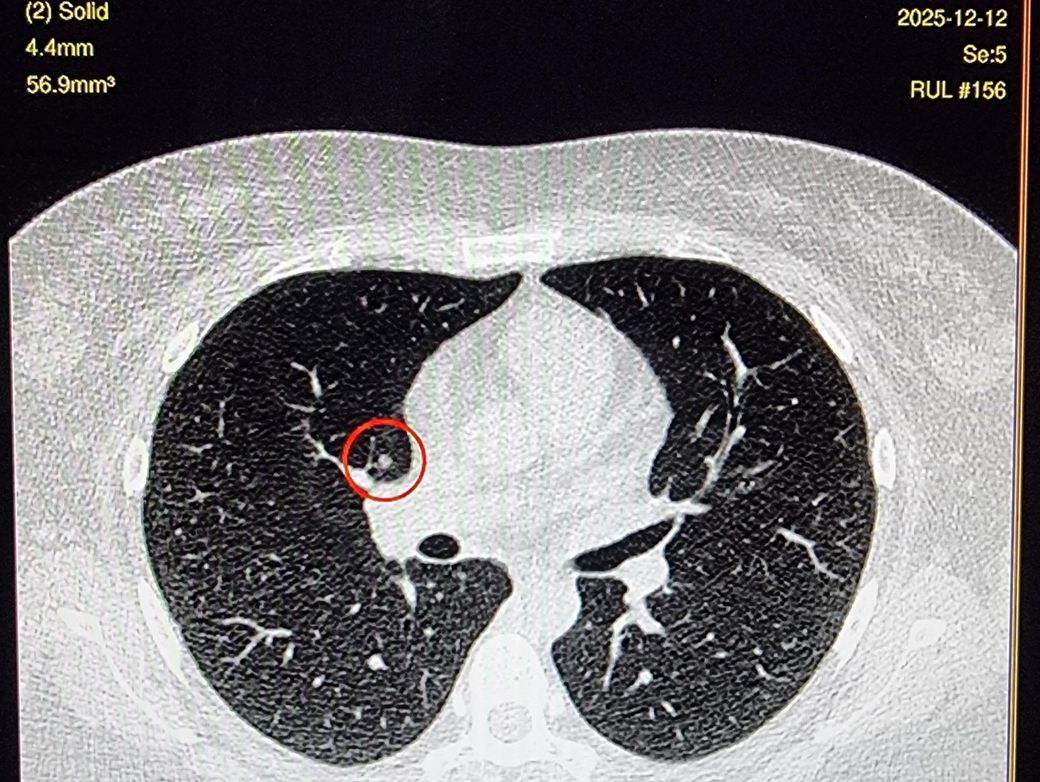

저선량 폐CT 영상보는데 이게 뭔가요? luCAS-plus

제 폐CT영상 잘받았나 확인하는데 끝에

이런게 있어요. luCAS-plus 항목에요.

CT에서 환자분이 말씀하신 것처럼 작은 결절은 한 커트만으로는 알 수 없고 여러 커트를 봐야 합니다.

어찌되었던 이 사진만 보면 결절처럼 보이기는 합니다.

하지만 결절은 위아래 사진을 같이 확인을 해보셔야 합니다.

한 커트에만 나와있다면 약간 애매하다 할 수 있습니다.